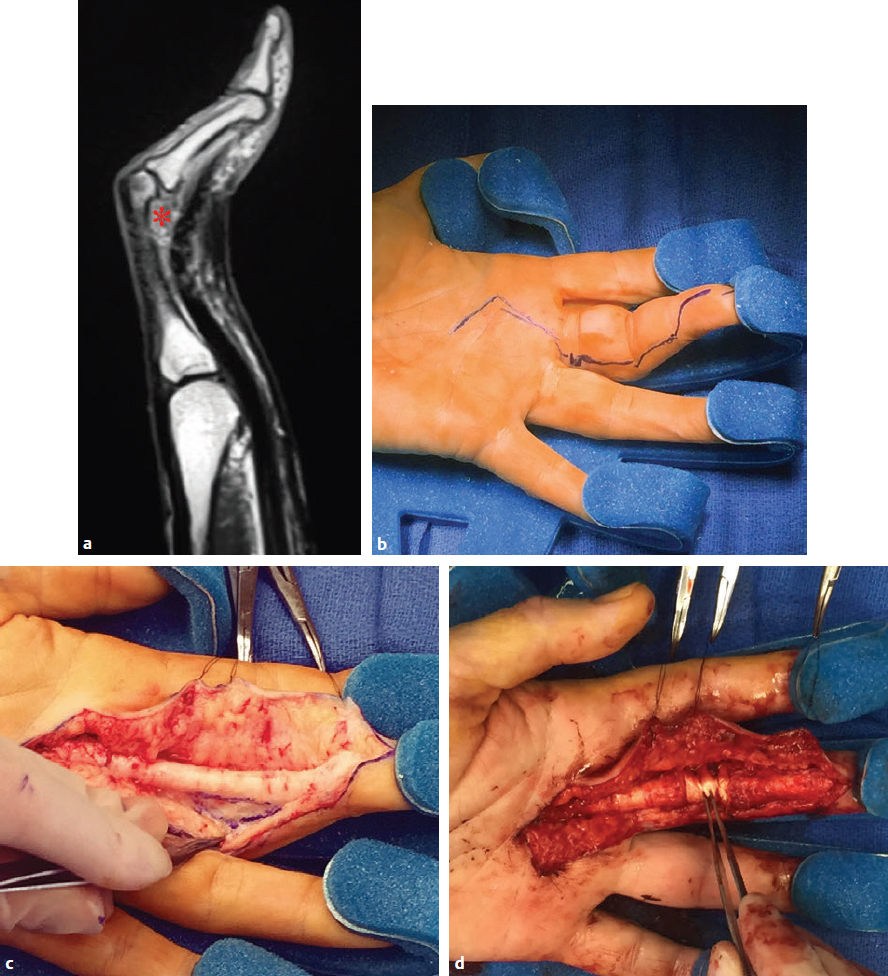

CHAPTER Although it is important to discuss the demographics and natural history of any disease, it is especially essential to do so with Dupuytren’s contracture or Dupuytren’s disease for risk assessment and potential avoidance of complications. These two terms refer to the same condition and may be used interchangeably. Dupuytren’s disease is a benign fibromatosis of the palmar digital fascia that has an autosomal dominant inheritance pattern with variable penetrance.1 Northern Europeans are more commonly affected than any other group, spawning nicknames such as “Viking’s disease” and “Celtic hand,” but all races and ethnicities have reported cases.2 Incidence is approximately 4% in the United States but is as high as 30% in Northern European countries.3,4 Dupuytren’s diathesis refers to a subset of patients with poor prognosis and a high risk of disease progression and recurrence. It was originally described by Hueston5 as individuals of Western European ancestry with a positive family history, bilateral involvement, and ectopic lesions. It was modified to include male gender and age at onset of younger than 50 years.6 The pathogenesis of Dupuytren’s disease can be divided into three stages: (1) proliferative, (2) involutional, and (3) residual.7,8 Formation of nodules begins in the early cellular proliferative stage. As disease progresses to the involutional stage, the nodules decrease in size and myofibroblasts predominate and follow lines of tension, which create cords. During the residual stage, nodules may completely disappear, and the fibrous cords thicken. Myofibroblasts largely disappear, leaving behind a hypocellular collection of type I and type III collagen. This third phase is when significant contractures may develop, and intervention may be required. The ring finger is most commonly involved, followed by the little finger, thumb, long finger, and index finger.1 The timing of intervention is an important consideration, because Dupuytren’s contracture follows an unpre dictable, fluctuating clinical course.1,9 With minimal joint contraction, cords may not be fully developed, and the extent of the disease may not have manifested. Operating early in the disease process can actually result in a postoperative contracture greater than the initial presentation.9 However, delaying treatment can also result in a severe contracture that may not be salvageable. The general consensus for intervention of Dupuytren’s contracture is metacarpophalangeal (MCP) joint contracture of 30 degrees or greater, or proximal interphalangeal (PIP) joint contracture of 20 degrees or greater with progression.1 The final consideration, which may prompt earlier treatment, is a patient with functional disability who is unable to carry out activities of daily living or recreational activities. The three primary treatment modalities currently used are fasciectomy, needle fasciotomy, and collagenase injection.10 Having the knowledge of the available methods along with their benefits and limitations is necessary to advise patients on the treatment plan most suitable for them. Patient comorbidities, occupation, lifestyle, and pattern of disease should all be taken into consideration. A healthy business executive with a busy travel schedule who presents with a single precentral cord is likely offered a different treatment option than a patient with multiple comorbidities who has diffuse palmar disease and multiple digit involvement. Fasciectomy can further be classified as open fasciectomy, dermofasciectomy, open palm fasciectomy, partial fasciectomy, and segmental fasciectomy.1 The traditional open fasciectomy is the excision of both normal bands and pathological cords. The aim of this approach is to prevent recurrence by excising fascia that may have the potential of developing into pathologic cords. This method is not commonly used and is outdated because of the high morbidity and no significant reduction in recurrence rates. Dermofasciectomy involves excision of the diseased fascia and the overlying skin with subsequent skin grafting.1,11 It was believed that the skin graft decreases the chance of recurrence by serving as a division between diseased and nondiseased fascia. The utility of this procedure is primarily in patients with recurrent aggressive disease and associated skin involvement or shortage. The open palm technique originally described by McCash12 is the excision of involved fascia through a combined transverse palm and zig zag finger incision with subsequent closure of the digital incision only. Most hand surgeons practice a modification of the McCash technique by leaving partial wounds open to avoid closing incisions tightly and compromising skin flap vascularity. The open palm technique remains a treatment option for diffuse palmar disease and multiple MCP contractures.13 Leaving the transverse incision open avoids skin grafting and allows for immediate active range of motion. Partial fasciectomy has long been the mainstay of surgical treatment for more severe contracture.1,10 Only the diseased fascia is removed under skin flaps. It is the treatment of choice for multiple digit involvement and recurrent Dupuytren’s contracture. Segmental fasciectomy is performed through multiple small transverse incisions, removing only segments of the cord to release the contracture while leaving behind the intercalary fragments. Its use is less common but it has the benefit of minimal surgical dissection and scarring.1 Needle fasciotomy can be performed in an office setting or outpatient treatment room without the need for sedation or tourniquet use, and the hand is prepped with antiseptic solution.14,15 Multiple portals should be marked longitudinally over the cord at a minimum of 5 mm apart. The procedure sequence is usually from distal to proximal portals. After injecting local anesthetic at the portal sites, a 25-gauge needle with the bevel oriented perpendicular to the cord fibers is used to pierce the skin through the dermis. A transverse fasciotomy is performed by sweeping the needle from side to side, advancing deeper with each sweep until the cord is fully released. The contralateral hand should be used to palpate the cord and apply gentle traction and passive extension of the finger. Multiple fasciotomies are performed at the portal sites until disruption of the cord is appreciated. Strenuous grip activities are avoided for 1 week. Postoperative therapy is usually not needed. Collagenase Clostridium histolyticum is a newer FDA-approved treatment for Dupuytren’s contracture.16,17 The two metalloproteinase enzymes work on all types of collagen, while sparing type IV collagen. Type IV collagen is prevalent in basement membranes of neurovascular structures, which offers the benefit of preserving arterioles, nerves, and epithelium with collagenase injection.17 Up to two separate cords can be injected simultaneously with reasonable efficacy. The 0.58-mg dose is diluted per specifications based on the site of injection and injected directly into the cord. The patient usually returns within 24 hours for gentle passive extension of the finger to initiate cord rupture. Patients should then be fitted for a nighttime splint to be worn for up to 4 months to maintain finger extension and instructed to perform finger extension and flexion exercises during that time. Summary Box Common Complications in Dupuytren’s Contracture Intervention • Neurapraxia and digital nerve injury • Skin necrosis and skin tears • Joint and scar contractures • Recurrence and disease progression • Complex regional pain syndrome and flare reactions • Flexor tendon transection and rupture Managing patient expectations before surgery is the first step in managing complications.1 Patients should be educated on the cause of Dupuytren’s disease and the possible recurrence and progression of the disease after correction. They should have a clear understanding of the expected outcomes and the limitations of the treatment, especially in the presence of substantial PIP contracture. The importance of the recovery period needs to be understood by the patient, because optimal functional outcome is dependent on the patient’s rehabilitation effort. Fig. 68.1 A spiral cord (black arrow) is clearly identified during fasciectomy of the middle finger Dupuytren’s contracture. Note the displacement of the digital neurovascular bundle (red arrow) by the spiral cord. To minimize the risk of neurovascular injury, the surgeon needs to have a thorough understanding of the anatomy. Proximal to the distal palmar crease, the digital nerves remain deep to the transverse fibers of the palmar fascia and can be dissected with assurance that the nerves do not wind around it.18 However, beyond the level of the distal palmar crease, the nerves can sharply turn over the top of the band and create a potential for injury. Normal fascial bands in the hand become cords when they are pathologically thickened and contracted.8 Recognition of the different types of cords is helpful to the dissection and prevention of accidental nerve injury10 (Fig. 68.1). Spiral, lateral, and abductor digiti minimi cords are known to displace the neurovascular bundle (NVB) superficially and to the midline. In the presence of a spiral cord, the structure first encountered at the digital flexion crease is often the NVB rather than the fascia of the cord.1 Dissection of the NVB should be started in the palm where the cords coalesce and followed to the palmar digital junction.1,18 Fasciectomy can be initiated by transecting the cord at the level of the superficial arch. It is found that release of the cords in the palm may help to partially correct the contracture and facilitate the dissection into the digit. If a digital artery injury is suspected, digital perfusion through the other digital artery should be evaluated by release of the tourniquet before skin closure. Vasospasm is the more common cause of transient digital ischemia.10 It is recommended to flex the finger to relieve traction, wrap the finger with warm saline-soaked sponges to improve capillary refill, and apply topical lidocaine or papaverine in the wound to facilitate smooth-muscle relaxation.19 Sufficient time should be allowed for interventions to work before formal exploration, because early dissection will further aggravate the vasospasm. Nerve injuries associated with needle fasciotomy are minimized with intradermal anesthesia because of preservation of sensory feedback.14 Patients should be assessed for fingertip sensitivity before and after local anesthesia and frequently throughout the procedure. Assessment of the skin overlying the cord may be helpful to prevent digital nerve injury. At the level between the distal palmar crease and the proximal digital crease, a spiral cord may be present that can cause medial and volar displacement of the neurovascular bundle.20 Unless the overlying skin is directly adherent to the cord, which would minimize the risk of an interposed digital nerve, caution should be taken at this level during needle fasciotomy. A Doppler examination should be performed if a spiral cord is suspected.14 Areas of identified Doppler tones should be marked to indicate where portal sites should be avoided. Injury to both digital arteries with needle fasciotomy is rare and preventable with thorough knowledge of the anatomy.10 Preoperative assessment of the quantity and quality of the skin is essential for incisional planning and wound closure. Skin necrosis is the most feared complication and is usually related to devascularization of a flap or to wound closure under tension.21 Rather than risking wound closure under excessive tension or using questionably viable flaps on exposed tendons, the central palm wound may be left open to heal by secondary intention. In the fingers, a midline longitudinal incision with z-plasty closure is preferred.21 The midline longitudinal incision ensures that the pedicle of the flap does not lie within the watershed area. Multiple z-plasties are advised to distribute tension and to provide a greater gain in length compared with a single z-plasty. When raising the skin flap, as much fatty subdermal layer as possible should be preserved to prevent vascular compromise (Fig. 68.2). However, if there is deep dermal involvement by Dupuytren’s disease, this may not be possible. Z-plasty should be avoided at the skin crease if possible, because this area often has minimal subcutaneous fat18 (Fig. 68.3). When there is skin shortage or potential for excessive tension under closure, alternative options may be to leave the wound open, skin graft, use a rotational flap, or even to use a heterodigital or cross-finger flap. Fig. 68.2 (a) Incision design with z-plasty flaps for contractures to adjacent fingers can only be safely performed if undermining is avoided and deep blood supply is preserved in critical areas. (b) By preserving perforating blood supply to this distally based flap and adjacent z-plasties, viability to skin flaps is ensured. (c) Tension-free closure is accomplished. Before wound closure, the tourniquet should be deflated to evaluate for flap viability and hemostasis.21 Evaluation for adequate hemostasis is important, because development of postoperative hematoma under the thin skin flaps can compromise flap viability. If uncertain about hemostasis, the surgeon may consider leaving the palmar incision open or placing a small, flat, soft drain. Skin tears are the most common complication, and it is not always possible to avoid them.20 Flexion creases are prone to skin tears and should not be used for portal sites.14 Places with redundant, mobile skin are the best areas for fasciotomy portals. At areas with nodular skin involvement, Eaton22 recommended dispersing the tension by using more portals, deferring definitive stretching until multiple portals have been released, and pushing on adjacent skin toward the firm area to protect it from the overall stretch. If a portal is beginning to tear, the surgeon might avoid further extension if it will propagate to an unmanageable wound. Fig. 68.3 The z-plasty should start with a midvolar longitudinal incision, because this lies in the “safe-zone” watershed area between the two digital arteries. Although a z-plasty as drawn by the solid line does not result in the transverse limbs being in the digital flexion crease, this may be a safer design than that created by the dotted lines because the thinnest part of the flap is then at the flexion crease directly across the base of the flaps. It is unnecessary to preferentially have the z-plasty flaps traverse precisely into the flexion creases. Skin tears are often sustained during a finger extension procedure. It is most common with MCP contracture greater than 50 degrees, especially if the skin overlying the cord is calloused.16 Meals and Hentz16 outlined a sequential four-step manipulation technique to minimize skin tears: 1. Flex the PIP joint while extending the MCP joint. 2. Flex the MCP joint while extending the PIP joint. 3. Extend both joints together. 4. Press on and disrupt any residual intact cords while keeping the finger extended under moderate tension. These steps can be repeated several times if necessary. If a skin tear is imminent, the surgeon may consider stopping and performing gentle passive progressive extension (Video 68.1). A clear understanding of the anatomical structures surrounding the interphalangeal (IP) joints is necessary to minimize persistent flexion contracture or lack of complete extension after fasciectomy.23 Curtis23 lists several mechanical factors that may limit the extension of the IP joints: • Inadequate skin over the volar surface of the finger • Fascia contractures within the finger • Contracture of the flexor tendon sheath within the finger • Contracted flexor muscles or adherent flexor tendons • Contracture of the volar plate • Shortening of the oblique retinacular ligament • Adherence of the accessory volar ligament to the neck and condyle of the proximal phalanx If there is greater than 30-degree residual PIP joint contracture after thorough resection of the involved fascia and flexor tenolysis, a volar plate release can be performed.23 If extension still cannot be obtained after volar capsulotomy, the oblique retinacular ligament can be excised on either side of the PIP joint. The surgeon may even make a conscious intraoperative decision not to perform volar release on any PIP joint contracture of less than 30 degrees, because many will relapse24 (Fig. 68.4). Final extension may then be accomplished with postoperative therapy. Fig. 68.4 (a) This patient with a little finger proximal interphalangeal (PIP) flexion contracture required not only fasciectomy but also volar joint release. Intraoperatively, the finger was able to gain full extension. (b) Postoperatively, the patient demonstrated full flexion of the fingers, but (c) the PIP joint remained painful and swollen. The PIP flexion contracture relapsed to 30 degrees. (d) In contrast, a patient with a similar little finger PIP flexion contracture did not require PIP joint release and was able to reach full extension by fasciectomy alone. Full postoperative flexion (e) and extension (f) was maintained. The morbidity commonly associated with joint release was avoided. Flexion deformity can occur if there is an imbalance of force between the extensor and flexor tendon. Powerful flexors readily overcome the chronically stretched and weakened extensor tendons of Dupuytren’s contracture and draw the finger into flexion.25 A nighttime extension splint may be required to correct the flexion deformity. A recent systematic review concluded that there is no efficacy in routine postop erative night splinting and that it is only indicated with early recurrent contractures.26 Flexor tendon bowstringing can also be a cause of flexion deformity because of the greater force applied by the flexors when important pulleys are accidentally resected during dissection.27 This reinforces the importance of finding the precise plane between the deep fascial dissection and the flexor sheath. Recurrence of flexion contracture, whether in a previously operated area or outside the surgical zone, does not necessarily indicate inadequate primary excision.28 It can represent a local progression of the disease or new disease in fascia outside the original operated area. Recurrence rates for each procedure vary greatly in the literature.29 The reason for this inconsistency is related to a lack of standard definitions of recurrence and a time point for reporting recurrence. A recent systematic review identified the range of recurrence rates to be 12 to 39% for fasciectomy, 50 to 58% for needle fasciotomy, and 10 to 31% for collagenase.30 Current available treatments are intended to release contractures rather than treat the underlying pathology; therefore recurrence is not unexpected and prevention is often not possible.1 Accurate identification of disease severity and careful preoperative planning is key to reducing further morbidity. Presenting contracture severity and number of involved digits are both correlated with complication rates and subsequent recurrence.30 Understanding of the disease prognosis will help to select which treatment options will be effective and be able to provide long-term benefit. An elderly patient with a single, palpable cord causing MCP joint contracture may benefit from a trial of needle fasciotomy or collagenase injection. Dupuytren’s diathesis may rather benefit from partial fasciectomy, because there is greater initial correction and lower recurrence rates compared with needle fasciotomy and collagenase injection.5,30 CRPS is more commonly reported after fasciectomy compared with needle fasciotomy and collagenase injection. It is also more prevalent in females.30 Diagnosis relies on clinical assessment, because there are no reliable or specific tests.31 It should be suspected in patients reporting pain out of proportion to what would be expected from the inciting event or that lasts beyond the average healing time for the injury. Individuals should be referred to a specialty pain clinic early for initiation of appropriate medications.10,31 Because it is difficult to identify the patients who will develop CRPS, it is recommended to take precautions in all patients during the perioperative period.32 Measures such as elevation of the hand to prevent swelling and providing adequate analgesia to minimize pain and anxiety should be applied. For patients who have severe disease and will require an extensive operation, it may be helpful to admit patients to the hospital after surgery for better postoperative pain control. The surgical management of coexisting Dupuytren’s disease and carpal tunnel syndrome was first studied by Nissenbaum and Kleinert33 in 1980. They reported an 87% complication rate in 15 patients who were treated with simultaneous carpal tunnel release and fasciectomy. Gonzalez and Watson34 later reported that there was no significant difference in complication rates in the combined group compared with fasciectomy alone. They recommended these two procedures be performed concomitantly when indicated to avoid an extra operation and progression of symptoms. A recent survey to the members of the American Society for Surgery of the Hand (ASSH)35 concluded that controversy remains among hand surgeons regarding this issue. A comparison of reported data on CRPS and stiffness did not find an increased rate of these two complications. Consequently, they concurred with the recommendations of Gonzalez and Watson. Postoperative extension splinting has been traditionally applied after fasciectomy to prevent recurrent joint contractures during the healing process. Studies have found that sustained tension to the healing tissues may promote local reactive changes, leading to excessive scar formation and flare reaction.36 Patients who exhibit flare reaction initially have a normal postoperative course followed by symptoms of pain, erythema, and stiffness during the third to fourth week after surgery. When placed in postoperative tension-free splints, the incidence of flare reaction was lower. It has been proposed that the mechanical stress on vessels causes decreased lumen diameter, which limits the oxygen delivery to tissues and promotes continued fibroblast formation, scarring, contracture, and possibly sympathetic flare. It was also found that delaying joint extension in the early wound-healing phases with tension-free splinting did not result in loss of motion gained from surgery.36 Flexor tendon injury is a rare complication after needle fasciotomy.10 If there is a suspicion that the needle is in the flexor tendon, a small amount of passive motion at the distal interphalangeal joint is applied to evaluate for movement of the needle with fingertip motion.14,15 If movement of the needle is observed or if the patient reports pain or paresthesia, the needle should be withdrawn and repositioned (see Chapter 61). Rare flexor tendon ruptures have been reported after collagenase injection to cords at the PIP joint of the little finger.37 Several modifications are recommended to avoid tendon ruptures. Before injection, the cord is palpated for the proximal and distal end to identify the midportion where the cord is maximally separated from the underlying tendon.16,17 The needle is then inserted in that area and care is taken to ensure that the needle does not go through the cord. For central cords, it is recommended to not inject more than 4 mm distal to the palmar digital crease and to insert the needle in a horizontal or coronal plane. For PIP joint contractures, it is advised to insert the needle close to the palmar digital crease and no more than 2 to 3 mm in depth (see Fig. 68.4). Many patients complain of numbness after surgery that is usually caused by digital nerve traction during dissection. This results in sensory neurapraxia, which is a transient nerve conduction block that typically improves within 6 to 12 weeks.38 A systematic review of outcomes for Dupuytren’s contracture reported neurapraxia occurring in 0.4 to 52% of cases with partial fasciectomy and 2 to 3% of cases with needle fasciotomy.30 Patients should have close follow-up, and if symptoms persist with no clinical improvement, they may benefit from appropriate diagnostic workup and possibly exploration.10 The incidence of digital nerve division ranged from 2 to 5% of cases with partial fasciectomy and in 0.4% of cases with needle fasciotomy.30 Digital nerve laceration should be repaired to improve sensation and to prevent persistent painful neuroma.32 End-to-end tension-free nerve coaptation remains the treatment of choice.39 When this is not feasible, a conduit can be used for gap lengths less than 10 mm and nerve graft can be used for longer gap lengths. Skin necrosis was reported to occur in 4.3 and 11.1% of patients undergoing fasciectomy for primary and recurrent Dupuytren’s disease, respectively.40 Small areas of skin necrosis will likely heal spontaneously and can be left open if there are no exposed tendons.41 Patients are encouraged to maintain active finger range of motion during the wound-healing phase, even in the presence of an open wound. A very large area of skin necrosis may result in slower healing, infection, or scar contracture. The surgeon may then need to perform an excisional débridement of the necrotic area and repair the defect with possible skin graft or flap. Fig. 68.5 The green zone indicates the safe area to inject a cord affecting the proximal interphalangeal (PIP) joint of the little finger. The red zone shows the danger area near the digital PIP joint crease where potential tendon rupture can occur if the needle is inserted. Skin tears are common after needle fasciotomy and collagenase injection, with rates ranging from 9 to 25% and 9 to 15% of cases, respectively.40 Fortunately, most skin tears heal uneventfully by secondary intention, even when accompanied by a small area of exposed flexor tendon. Avoidance of tendon desiccation is achieved by application of medicated ointment two times a day and wrapping the wound with an adhesive strip bandage until the skin edges are approximated by secondary healing.15 Skin tears rarely need to be closed primarily or require skin grafting. Minor bleeding is not uncommon, and patients are advised to apply gentle pressure, change the dressing as needed, and continue full active finger range of motion during the wound-healing phase. Joint contracture after fasciectomy has been reported to occur in 6.7% of cases and predominantly involves the PIP joint.40 PIP joint contracture may be secondary to extrinsic causes such as skin contracture or diseased palmar-digital fascia.38 The patient in Fig. 68.5 had multiple prior Dupuytren’s contracture releases to the little finger and developed a significant scar contracture. He had a large soft tissue deficit after scar excision that required local tissue rearrangement with multiple z-plasties and an arterialized heterodigital flap from the left ring finger to the palm. PIP joint contracture can also be related to an intrinsic source, such as adhesions to the flexor sheath, tendons, volar plate, or collateral ligaments.38 Intrinsic joint release is an option for a severely contracted PIP joint that is not corrected by fasciectomy alone. As previously mentioned, it is acceptable to not perform volar capsulectomy for PIP contractures of less than 30 degrees, because these will likely relapse.24 Severe, dysfunctional contractures may require salvage procedures such as PIP joint fusion or even ampu tation. The patient in Fig. 68.6 previously had Dupuytren’s contracture release to the left little finger and developed PIP joint contracture. A heterodigital flap was required from the adjacent ring finger to fill in the very large wound and skin deficit during the revision surgery. Another patient (Fig. 68.7) required little finger PIP joint arthrodesis for severe recurrent flexion contracture. The large PIP and volar finger soft tissue deficit was covered with a cross-finger flap. Fig. 68.6 (a) This 61-year old patient developed a severe scar contracture of the little finger after multiple Dupuytren’s contracture releases. (b) After scar excision and release, a template of the large soft tissue wound in the distal palm was created with a rubber Esmarch bandage. (c) A heterodigital vascularized island flap from the left ring finger was dissected back to the branch point of the common digital artery. (d) The flap was transposed to the palm and inset. A groin full-thickness skin graft was used for closure of the donor defect. Early postoperative demonstration of finger flexion (e) and extension (f,g). The patient will need therapy to achieve full PIP flexion and extension. Fig. 68.7 (a) A 73-year-old patient who previously had Dupuytren’s contracture release of the little finger developed a severe flexion proximal interphalangeal (PIP) joint contracture into the palm. (b) A soft tissue deficit on the volar aspect of the little finger was left after PIP arthrodesis. (c) A cross-finger flap from the adjacent left ring finger was used for coverage. (d) The long-term outcome after division of the cross-finger flap with resolution of PIP flexion contracture. Flexor tendon bowstringing is a rare complication. It may be more common in recurrent Dupuytren’s contracture when the flexor tendon sheath is not identified within the scar and is accidentally disrupted.38 Fig. 68.8 shows a patient who had disruption of the A2 pulley resulting in PIP flexion contracture and bowstringing of the left middle finger. He had release of PIP flexion contracture and flexor tendon pulley reconstruction with a tendon graft. Wide-awake tumescent local anesthesia is useful so that full functional correction can be assessed by patient activity (Video 68.2). Although the recurrence rate is highly variable, it is well-established that the overall recurrence rate for partial fasciectomy is lower compared with needle fasciotomy and collagenase injection.30 Repeat surgery for Dupuytren’s contracture presents a challenge for hand surgeons. The anatomy is often distorted because of adherent scar tissue, making dissection difficult and the potential for neurovascular injuries more likely. Therefore reoperation for Dupuytren’s contracture should be preceded by a thorough assessment and planning.1,38 Evaluation of previous incisions and extent of soft tissue contracture may help to anticipate the need for skin grafting and possible flap to achieve wound closure. Identification of previously injured nerves and vessels is helpful. This is done by thorough sensory assessment and a digital Allen test. Patients should once again be counseled on realistic outcomes and the potential for recurrence. They should be warned that postoperative therapy may be more extensive. When compared with partial fasciectomy, the recurrence rate of needle fasciotomy was significantly higher based on a 5-year follow-up from a randomized control trial (84.9 versus 20.9%).42 Patients who developed recurrent disease after needle fasciotomy were offered a second treatment with needle fasciotomy or partial fasciectomy. On average, 50% of the patients treated with repeat needle fasciotomy developed a second recurrence after 4.4 years. Based on these findings, the authors concluded that needle fasciotomy is an effective alternative treatment for recurrent Dupuytren’s disease as long as patients are willing to accept the higher recurrence rate for the benefit of shorter recovery time and less invasiveness.